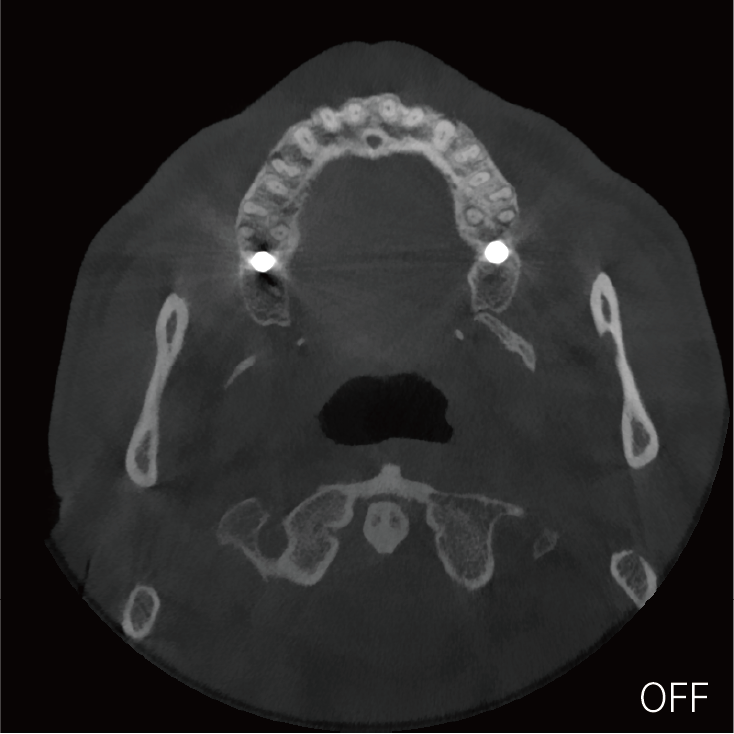

支持局部超清三维显示

局部超清显示、 移动视野摄片

可根据临床需求任意调整成像区域大小实现局部超清三维显示

临床样片